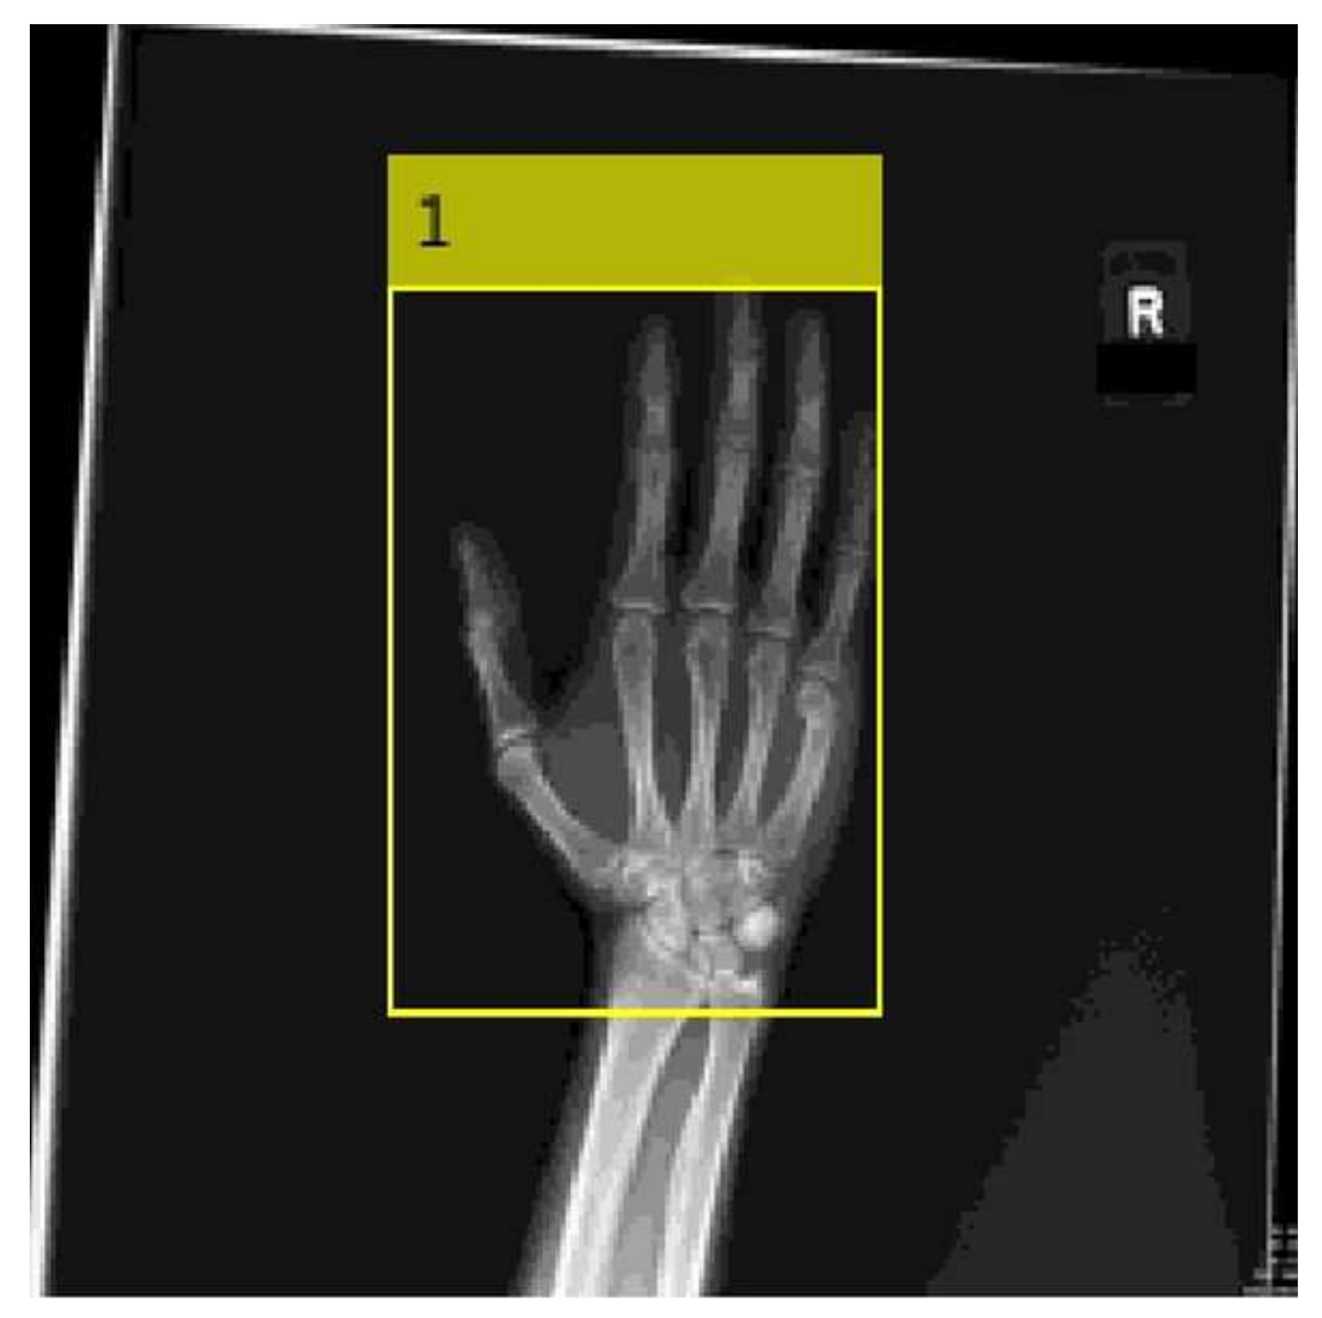

The trained CNN detector (Figure 1) was used to automatically place a bounding box over the hand anatomy on an additional 100 frontal, oblique and lateral hand radiographs, which were not used for training or validation. A computer algorithm further processed each output image to calculate top, bottom, right and left air density spaces on the radiographs.

Figure 1. Example of CNN detector output image with bounding box placed over the hand. Pixelation of the image is due to the decrease in the size of the original radiograph to a smaller image size, which is suitable for CNN training and processing.